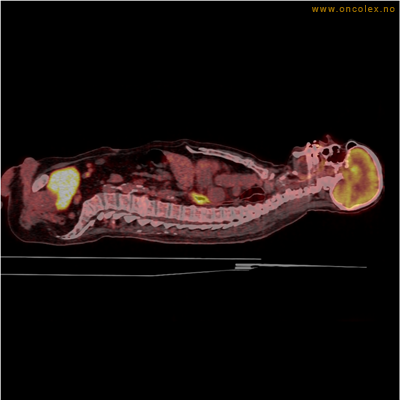

Eksempler på funn

Vev som tar opp mer radioaktivt stoff, synes som hvite områder som lyser opp mer i forhold til annet vev som tar opp mindre sukker.

Kraftig opptak i svulst i lunge.

Lungekreft med spredning til lymfeknute i lungehilus.